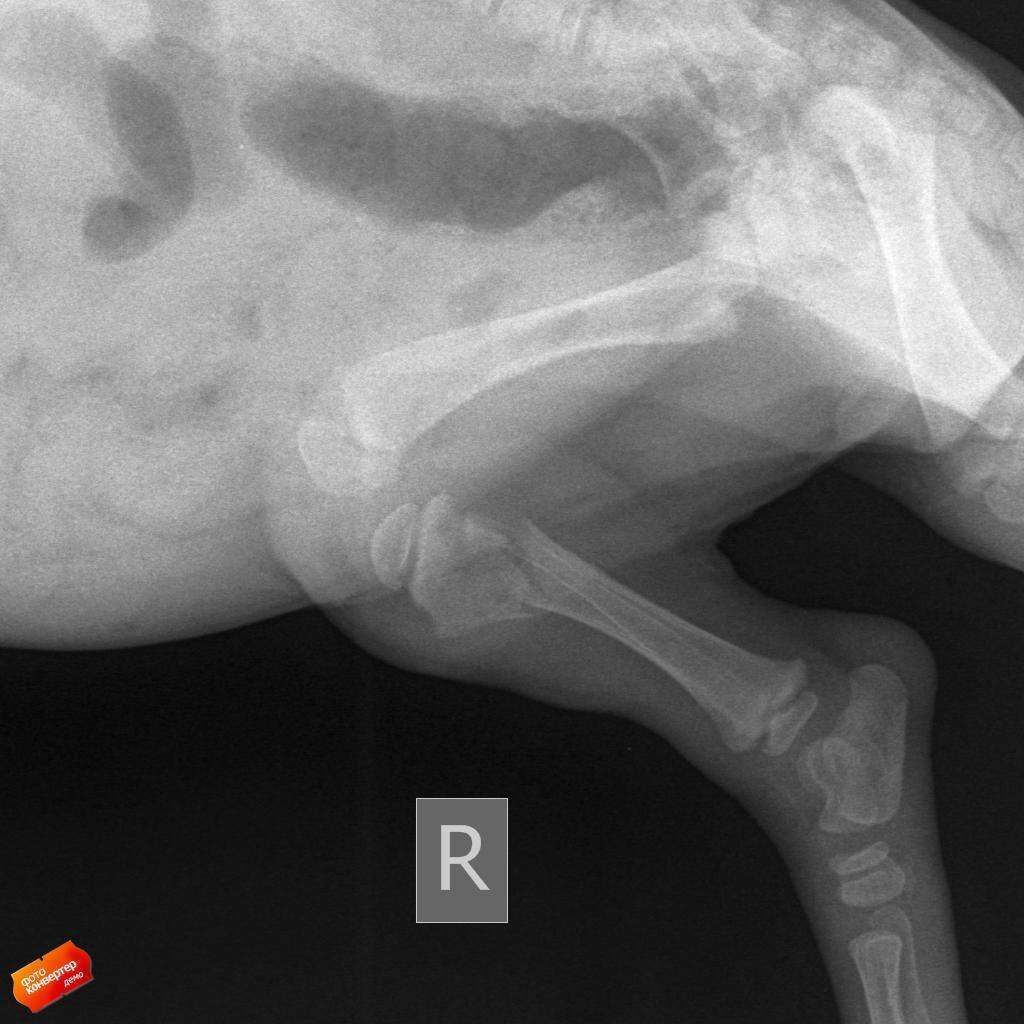

У одного щенка отказали лапки, у другого щенка - перелом со смещением.

В настоящее время один щенок - Тишка находится в тяжелом состоянии - у мальчишки отказали задние лапы. Точный диагноз нам пока поставить не могут, но склоняются к инфекции. Тишка сейчас находится на бесплатной передержке, где его лечат. Необходимы деньги на корм малышу и лекарственные препараты.

Второй щенок - Сонька сломала лапу - перелом со смещением. Сейчас пьет витамины и скоро необходим контрольный рентген.